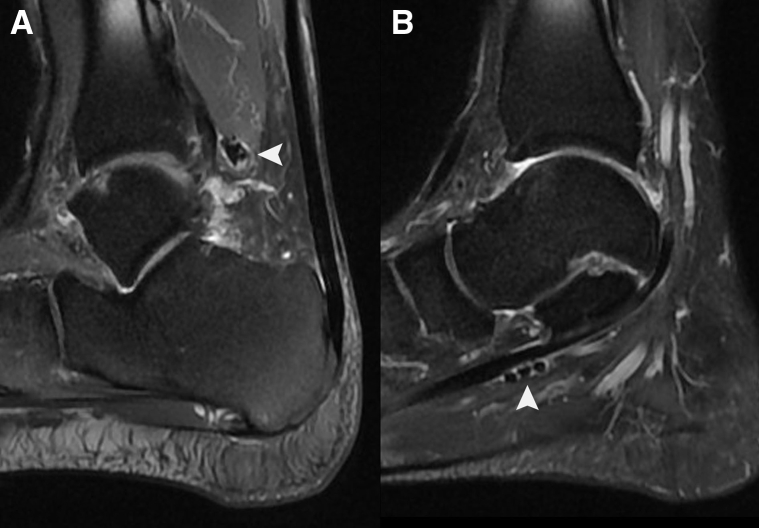

Preoperative magnetic resonance imaging (MRI) is important for gauging the extent of disease and surgical planning (Fig 1). The location of the loose bodies can be identified on MRI. MRI is particularly useful in those cases in which plain radiography cannot show calcifications or ossifications.12

Fig 1.

Sagittal views on magnetic resonance imaging of the right ankle in the illustrated case. (A) Loose bodies (arrowhead) at the zone 1 flexor hallucis longus posterior to the ankle. (B) Loose bodies (arrowhead) at the zone 2 flexor hallucis longus tendon sheath.